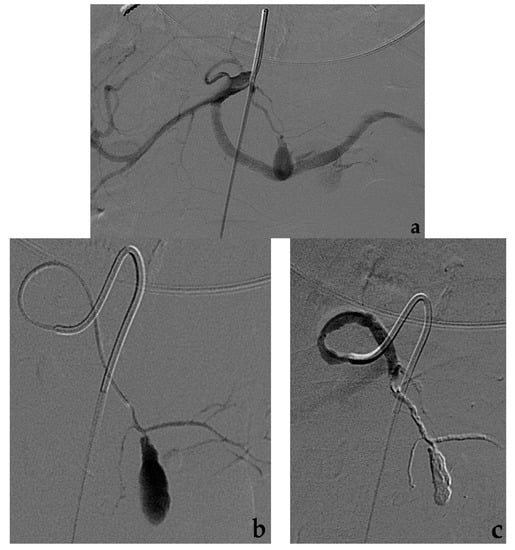

- Modestino, F.; Cappelli, A.; Mosconi, C.; Peta, G.; Bruno, A.; Vara, G.; De Benedictis, C.; Golfieri, R. Balloon-assisted coil embolization of a wide-necked aneurysm of the inferior pancraticoduodenal artery. CVIR Endovasc. 2020, 3, 62. [Google Scholar] [CrossRef] [PubMed]

- Onal, Y.; Samanci, C.; Cicek, E.D. Double-lumen balloons, are they only useful in neurointerventions? Preliminary outcomes of double-lumen balloon-assisted embolization of visceral artery aneurysms. Vasc. Endovasc. Surg. 2020, 54, 214–219. [Google Scholar] [CrossRef]